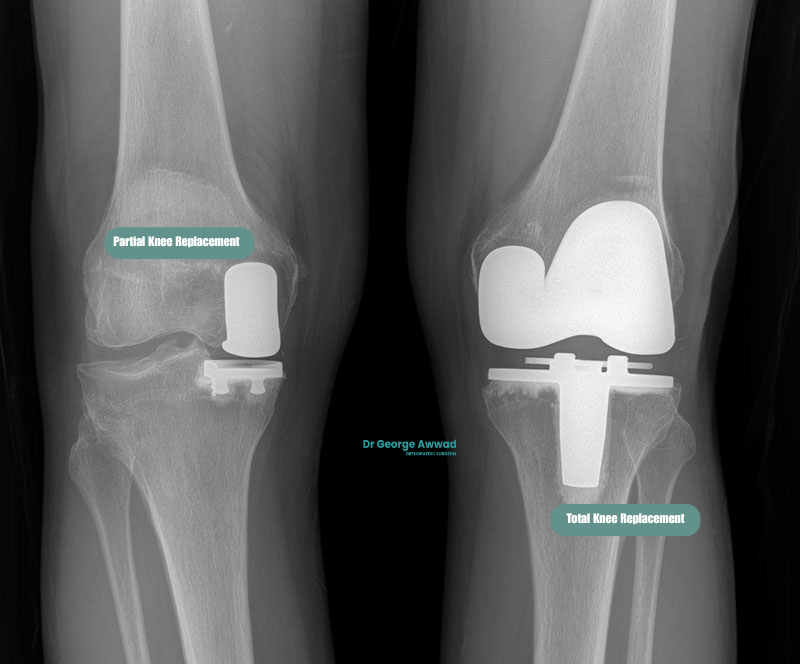

Partial knee replacement surgery, also known as unicompartmental knee arthroplasty, is a surgical procedure used to treat arthritis that affects only one part of the knee joint. Unlike total knee replacement, which replaces the entire joint surface, a partial knee replacement involves resurfacing only the damaged compartment, typically the medial (inner), lateral (outer), or patellofemoral (kneecap) region, while preserving healthy bone, cartilage, and ligaments.

A partial knee replacement, also known as unicompartmental or, hemi knee arthroplasty, is a surgical procedure used to treat arthritis or damage that is limited to a single compartment of the knee joint. Unlike a total knee replacement, which replaces all the surfaces of the knee, a partial knee replacement targets only the affected area, either the medial (inner), lateral (outer), or patellofemoral (kneecap) compartment.

What are the benefits of partial knee replacement compared to total knee replacement?

Smaller incision and less disruption to soft tissue

Faster recovery and shorter hospital stay

Partial knee replacement may involve a shorter hospital stay and a faster return to walking and daily activities. Many patients experience less post-operative pain and swelling compared to total knee replacement, which may help them progress more quickly through early rehabilitation.

More natural knee motion

Preserving the unaffected parts of your knee may allow for more natural joint mechanics. Some patients report that their knee “feels more normal” after partial replacement compared to a total knee prosthesis, particularly with activities that require balance or coordination.

Reduced blood loss and lower risk of complications

Potential for future total knee replacement if needed

Partial knee replacement vs total knee replacement: which is right for you?

If you’re living with knee arthritis, one of the most important decisions in your treatment journey is whether to have a partial knee replacement (PKR) or a total knee replacement (TKR). Both procedures aim to relieve pain and improve function, but they differ in terms of surgical approach, recovery, and long-term considerations. The most appropriate option for you depends on the extent of arthritis in your knee, your overall health, lifestyle, and goals.

Key differences between partial and total knee replacement

| Feature | Partial Knee Replacement (PKR) | Total Knee Replacement (TKR) |

|---|---|---|

| Extent of arthritis treated | One compartment only (typically medial, lateral, or patellofemoral) | Two or more compartments (always medial and lateral; patellofemoral joint may or may not be resurfaced) |

| Tissue preservation | Preserves more bone and ligaments | Replaces all joint surfaces and sometimes removes ligaments |

| Surgical invasiveness | Smaller incision, less bone removal | Larger incision, more comprehensive reconstruction |

| Recovery time | Generally faster recovery and shorter hospital stay | Longer initial recovery, more extensive physiotherapy |

| Knee function | Often retains more natural movement and feel | Reliable pain relief, but may feel more artificial |

| Suitability | Best for patients with isolated compartment arthritis | Suitable for widespread arthritis across the entire knee |

| Revision risk | May require conversion to TKR in future if arthritis spreads | Typically lasts longer with fewer additional surgeries required |